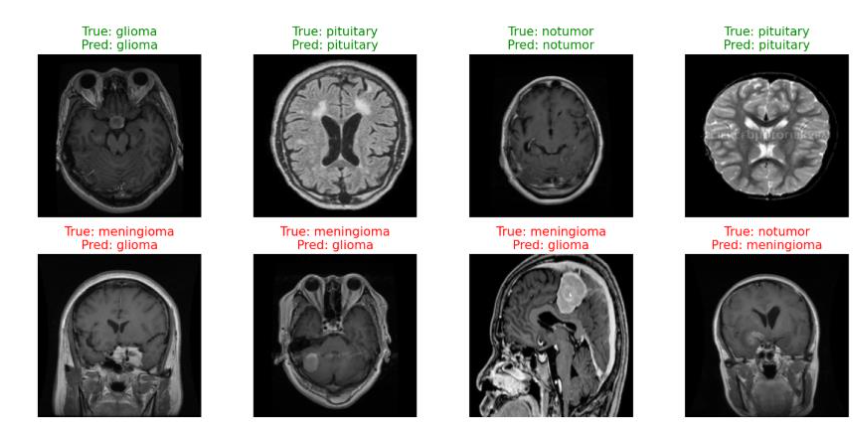

5.3 Confusion Matrix and Classification Report

The confusion matrices shown in Figure 6 provide a visual representation of classification outcomes for both models on the test dataset. The ResNet18 model demonstrates exceptional performance, achieving near-perfect classification across all tumor categories—glioma, meningioma, pituitary tumor, and no tumor—indicating excellent generalization and discriminative feature learning. In contrast, the custom CNN model exhibits slightly higher misclassification rates, particularly between glioma and meningioma samples, where subtle morphological similarities in MRI features led to occasional confusion.

These results highlight the advantage of transfer learning in extracting deeper hierarchical representations and capturing complex spatial dependencies inherent in MRI data. The ResNet18 model’s residual connections facilitate improved gradient flow and feature reuse, leading to more stable and accurate learning compared to the baseline CNN trained from scratch.

Qualitative inspection of model predictions in Figure 13 further illustrates the improved delineation of tumor regions and more reliable classification. However, error analysis revealed that both models struggled with low-contrast or ambiguous tumor boundaries, suggesting that subtle lesions remain challenging for 2D architectures. These findings align with prior research highlighting the importance of transfer learning for medical image analysis and emphasize the need for models capable of capturing deeper context and multimodal information.